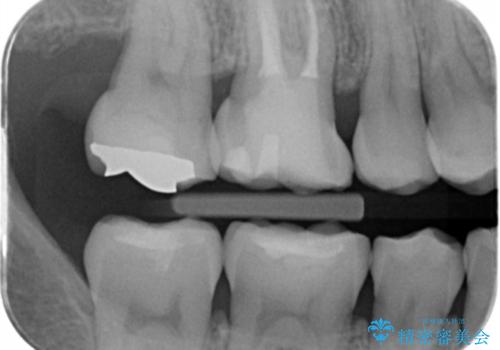

不適な樹脂の詰め物 被せ物で被覆

- 奥歯の劣化・変色した樹脂の詰め物をやり直していきます。

セラミックのインレーでは強度に不安が残るため、セラミッククラウンで全体を被覆することとしました。